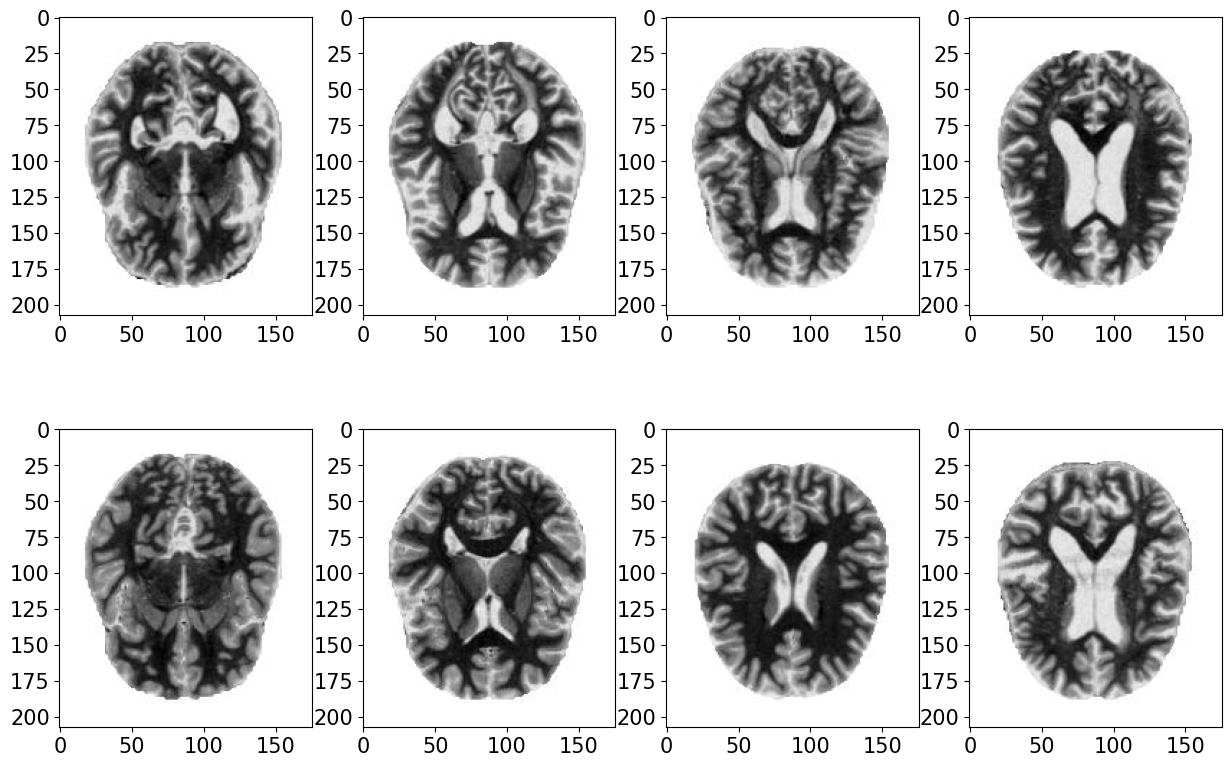

AD is distinguished by a progressive and seemingly continuous pathological progression, marked by the development of neurodegeneration exhibiting distinct spatial and temporal dynamics. Specific characteristics can strongly indicate the diagnosis of AD. In AD, the brain typically exhibits at least moderate cortical atrophy, particularly pronounced in multimodal association cortices and limbic lobe structures. Structural neuroimaging with MRI can be employed to evaluate atrophy as a metric of neurodegeneration in AD. We conduct our experiment on dataset originates from https://www.kaggle.com/datasets/kaushalsethia/alzheimers-adni (Samples in Figure 7).

Due to the difficulty of detecting the tipping point in high-dimensional time series, we need to reduce the dimension of brain MRI data to the plane. Firstly, the Variational AutoEncoder (VAE) [68] model is employed to extract features from the representation space, educing the image data to 20-dimensional vectors. Subsequently, these 20-dimensional vectors are projected into a 2-dimensional space utilizing the t-distributed Stochastic Neighbor Embedding (t-SNE) [69] method. The following is the visualization of healthy and AD patients after VAE and t-SNE reduction (Figure 7).

We employed reduced MRI images from 1100 healthy individuals as the initial distribution and from 750 AD patients as the target distribution. The pathway dynamics from the initial to the target distribution are established via the Schrödinger Bridge theory, which could be viewed as an entropy-regularized optimal transport problem. To identify the tipping point from the healthy brain state to the AD brain state, we compute the estimates of and density via the loss function described in Eq.(21).

The embedding densities of the two datasets can now be employed to compare tipping phenomena. From Figure 8, we can see the time evolutionary density from healthy state to Alzheimer state. The consistent evolution of the first and second rows across steps in Figure 8 represents that the determined density involution converges, a theoretical guarantee provided by [13, 70]. It’s obvious that the geometric of samples undergoes a sudden change between 15-th and 20-th steps, aligning with the abrupt tipping indicated by our defined indicator in (24). That implies that a critical transition in the brain state occurs between the 15-th and 20-th step, emphasizing the need for intervention prior to the tipping point.